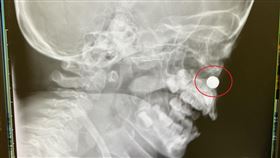

2歲童想吐流膿 就醫才知電池卡鼻腔

一名2歲小男童上午一直有想嘔吐的感覺,家長懷疑吃到異...